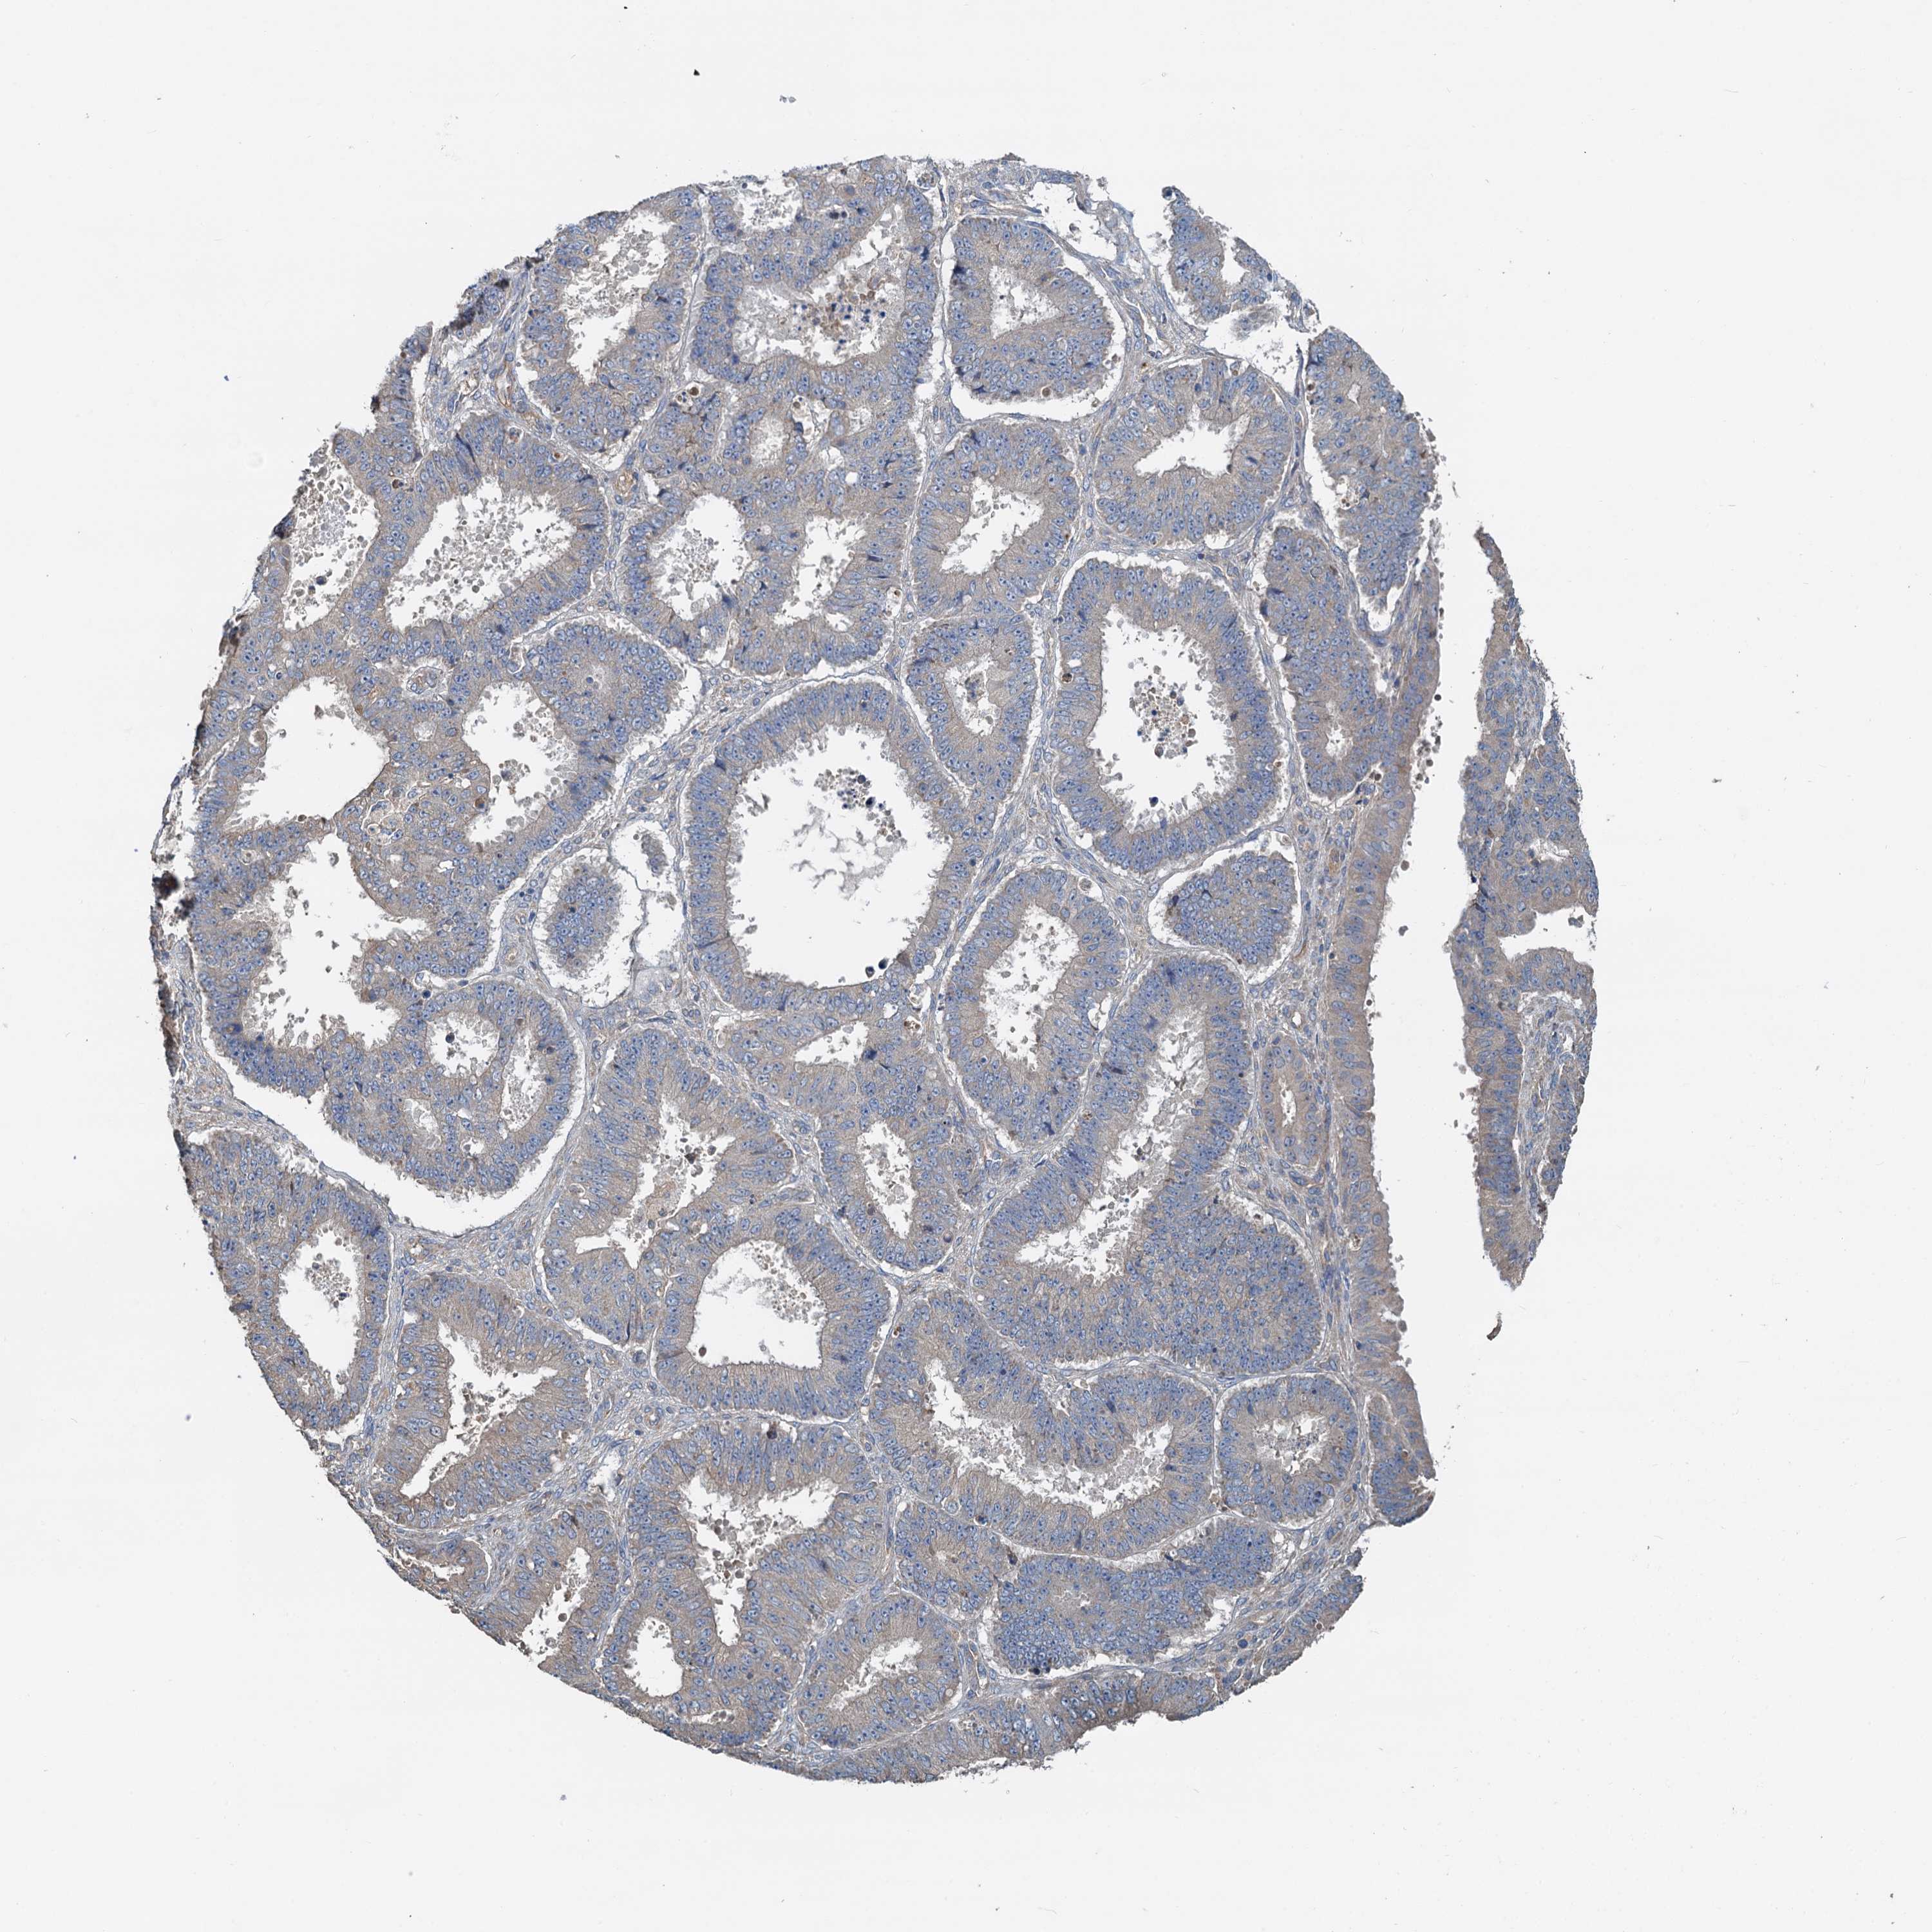

OVARIAN CANCER - Protein expressioni

A mouse-over function shows sample information and annotation data. Click on an image to view it in a full screen mode. Samples can be filtered based on level of antibody staining by selecting one or several of the following categories: high, medium, low and not detected. The assay and annotation is described here.

Note that samples used for immunohistochemistry by the Human Protein Atlas do not correspond to samples in the TCGA dataset.

Antibody stainingi

Antibody staining in the annotated cell types in the current human tissue is reported as not detected, low, medium, or high, based on conventional immunohistochemistry profiling in selected tissues. This score is based on the combination of the staining intensity and fraction of stained cells.

Each image is clickable and will lead to virtual microscopy that enables deeper exploration of all samples and also displays staining intensity scores, fraction scores and subcellular localization as well as patient and tissue information for each sample.

Antibody HPA040092

Staining

High

Medium

Low

Not detected

Intensity

Strong

Moderate

Weak

Negative

Quantity

>75%

75%-25%

<25%

None

Location

Nuclear

Cytoplasmic/membranous

Cytoplasmic/membranous,nuclear

Cystadenocarcinoma, serous, NOS

Carcinoma, endometroid

Cystadenocarcinoma, mucinous, NOS

Carcinoma, NOS